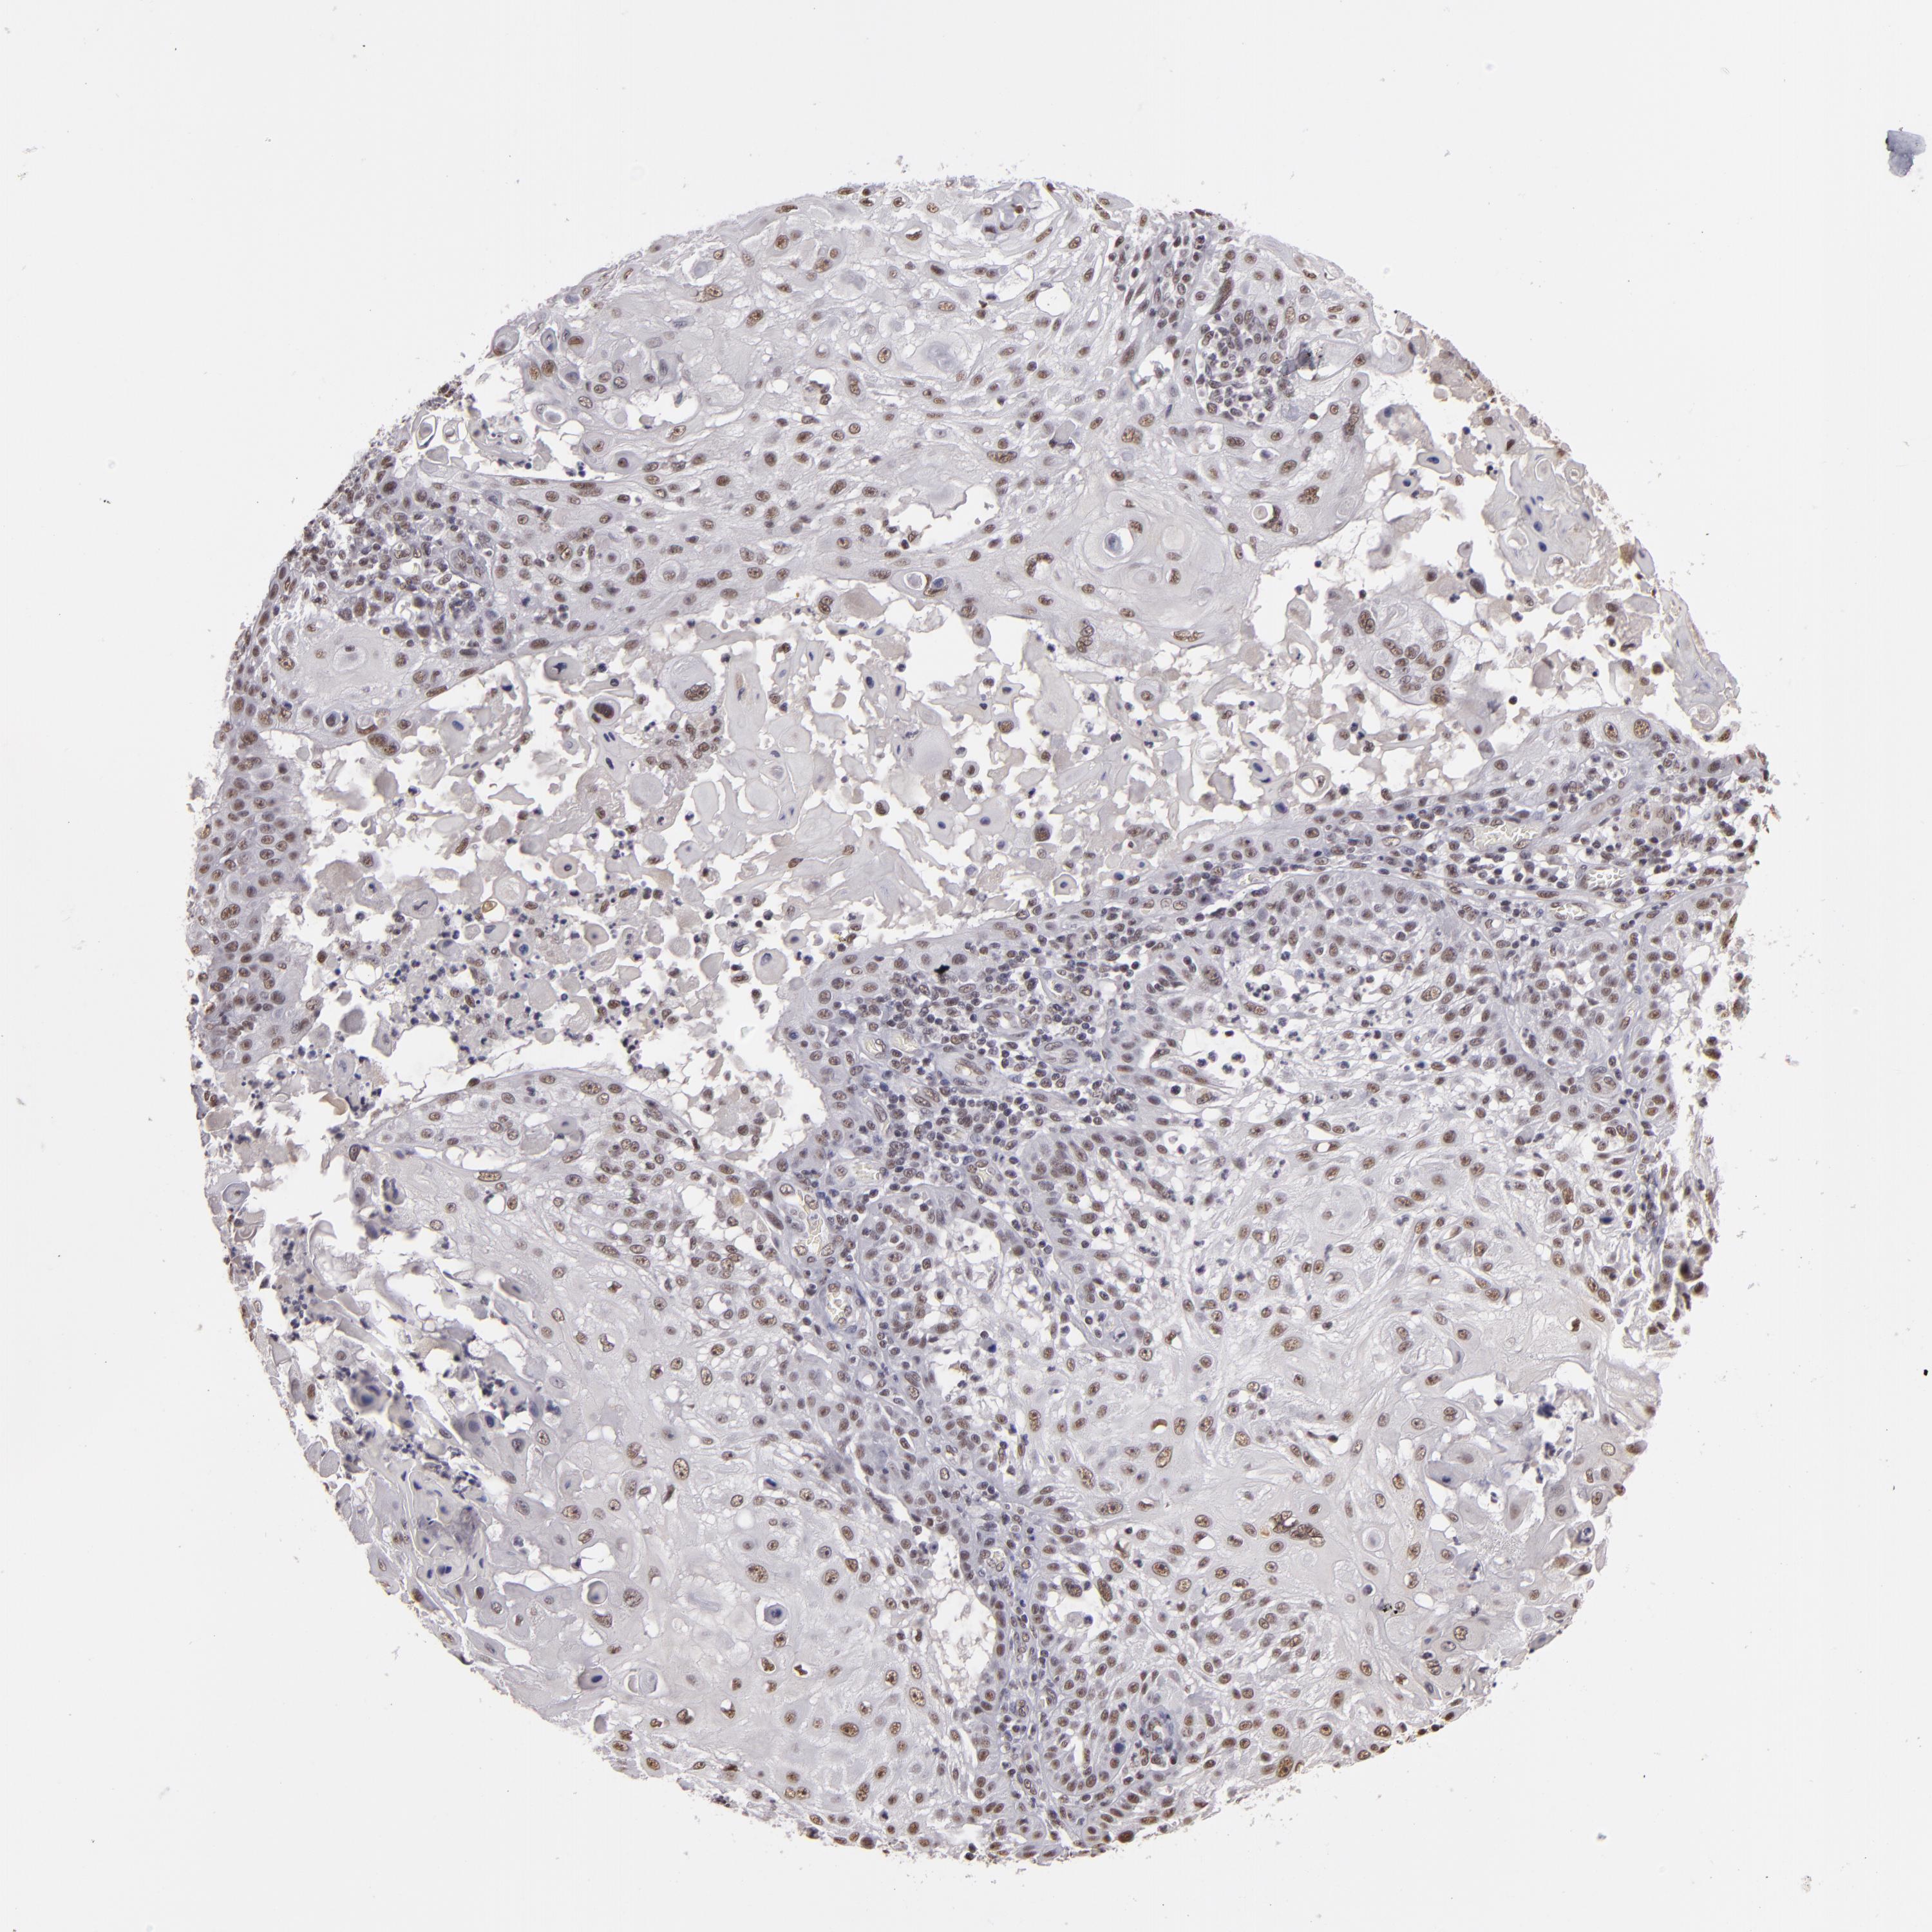

SKIN CANCER - Protein expressioni

A mouse-over function shows sample information and annotation data. Click on an image to view it in a full screen mode. Samples can be filtered based on level of antibody staining by selecting one or several of the following categories: high, medium, low and not detected. The assay and annotation is described here.

Antibody stainingi

Antibody staining in the annotated cell types in the current human tissue is reported as not detected, low, medium, or high, based on conventional immunohistochemistry profiling in selected tissues. This score is based on the combination of the staining intensity and fraction of stained cells.

Each image is clickable and will lead to virtual microscopy that enables deeper exploration of all samples and also displays staining intensity scores, fraction scores and subcellular localization as well as patient and tissue information for each sample.

Antibody HPA001846

Staining

High

Medium

Low

Not detected

Intensity

Strong

Moderate

Weak

Negative

Quantity

>75%

75%-25%

<25%

None

Location

Nuclear

Cytoplasmic/membranous

Cytoplasmic/membranous,nuclear

Squamous cell carcinoma, NOS